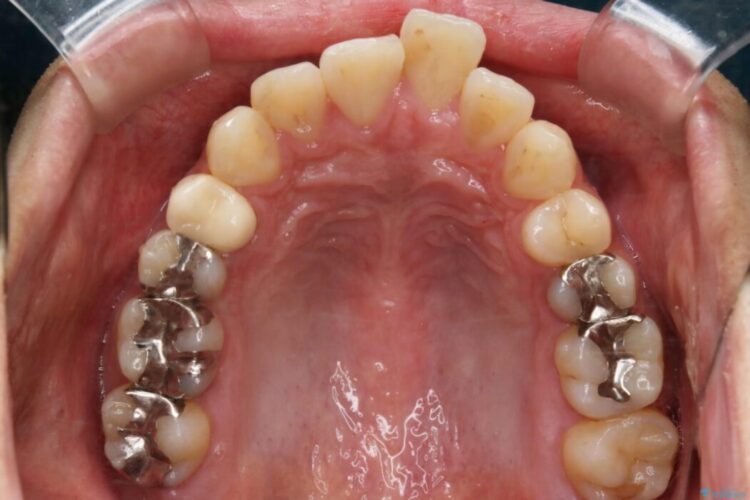

本症例では上顎前突(出っ歯)や歯列のがたつきを改善するスペースを確保するために、歯を遠心移動をサポートすることができるマイクロインプラントを用いたゴムかけを行っていただきました。

それにより従来の矯正治療と比べましても効率的に歯の移動を行えるため、非抜歯の場合でも歯列を整えることが可能となります。